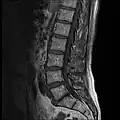

MRI lumbar spine with degeneration (sagittal T2 FRFSE) -

MRI lumbar spine with degeneration (sagittal T1 FSE) -

MRI lumbar spine with degeneration (sagittal FAST STIR) -

MRI lumbar spine pre-hemilaminectomy (sagittal T2 FRFSE)

MRI lumbar spine pre-hemilaminectomy (sagittal T1 FSE)

MRI lumbar spine pre-hemilaminectomy (sagittal FAST STIR)

MRI lumbar spine post-hemilaminectomy (sagittal T2 FRFSE)

MRI lumbar spine post-hemilaminectomy (sagittal T1 FSE)

Contrast MRI lumbar spine post-hemilaminectomy (sagittal T1 FSE FS)